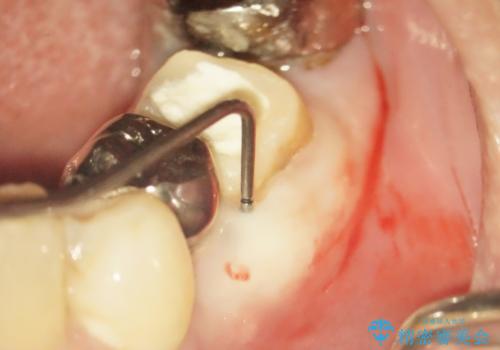

- 右下の奥歯でものを咬むと違和感があるので診て欲しいといらっしゃった方の症例です。

右下6は神経が死んでいたため根管治療を行い、オールセラミッククラウンによる補綴を行いました。

- 根管治療により痛みや腫れがひかない事や、術後に痛みや腫れが生じる事、治療によるファイル破折やパーフォレーションなどの偶発症、術後の歯根破折を生じる可能性もあります